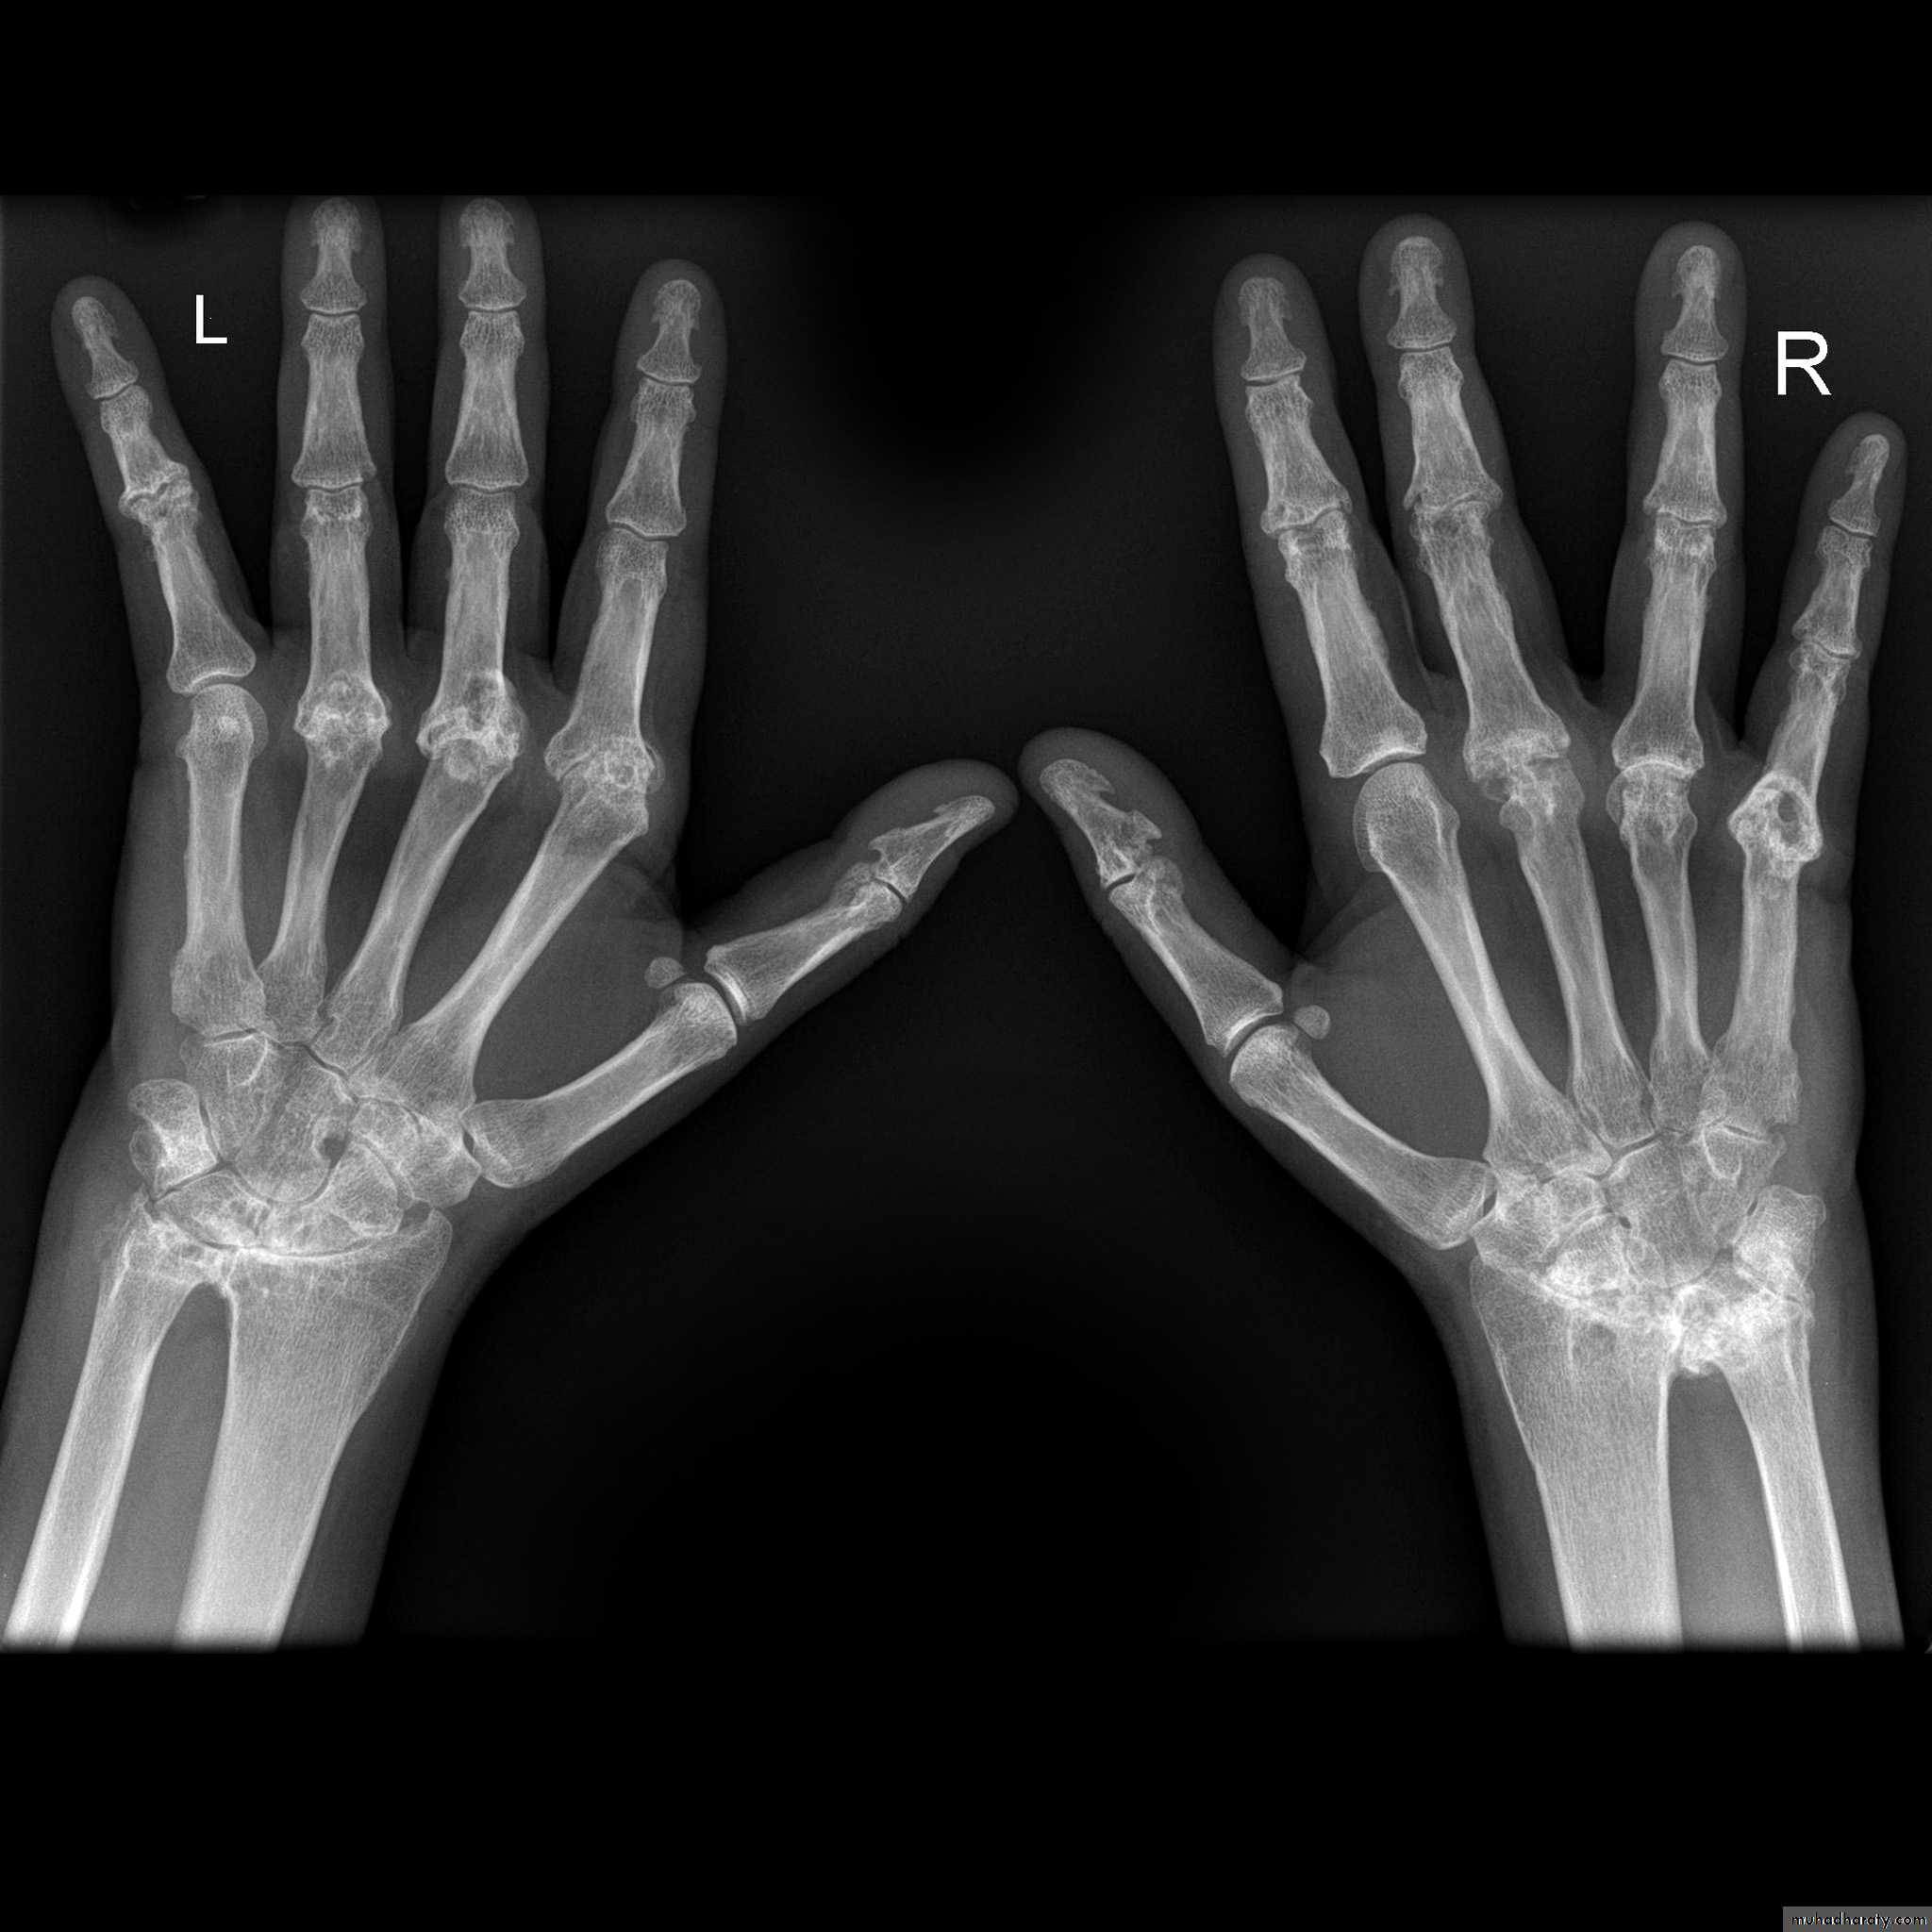

Rheumatoid arthritis.

(A) The initial radiograph shows a hint of early trabecular loss around the proximal interphalangeal joint of a finger with preservation of the joint space and early marginal cortical loss at thebase of the middle phalanx.

(B) The subsequent radiograph shows established erosive change in the area of ill-defined demineralisation in association with joint space narrowing .

Gross rheumatoid arthritis at the carpus with ulnar deviation,

subluxation and joint narrowing at the metacarpophalangeal joints.Boutonniere deformities are present at the index and little fingers.

• Rheumatoid arthritis. Bilateral changes are fairly symmetrical. Soft-tissue swelling is demonstrated, especially over the ulnar styloids. Erosions are demonstrated at the carpus, distal radius and ulna, with joint space narrowing and collapse of bone. Metacarpophalangeal erosions are also seen associated with joint space narrowing. There is a swan-neck deformity of the right fifth distal interphalangeal joint